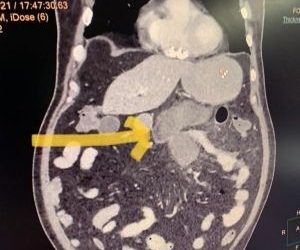

Read moreDetailsNew Delhi: A novel complication of mucormycosis or black fungus has been detected in a city hospital here in which the ...